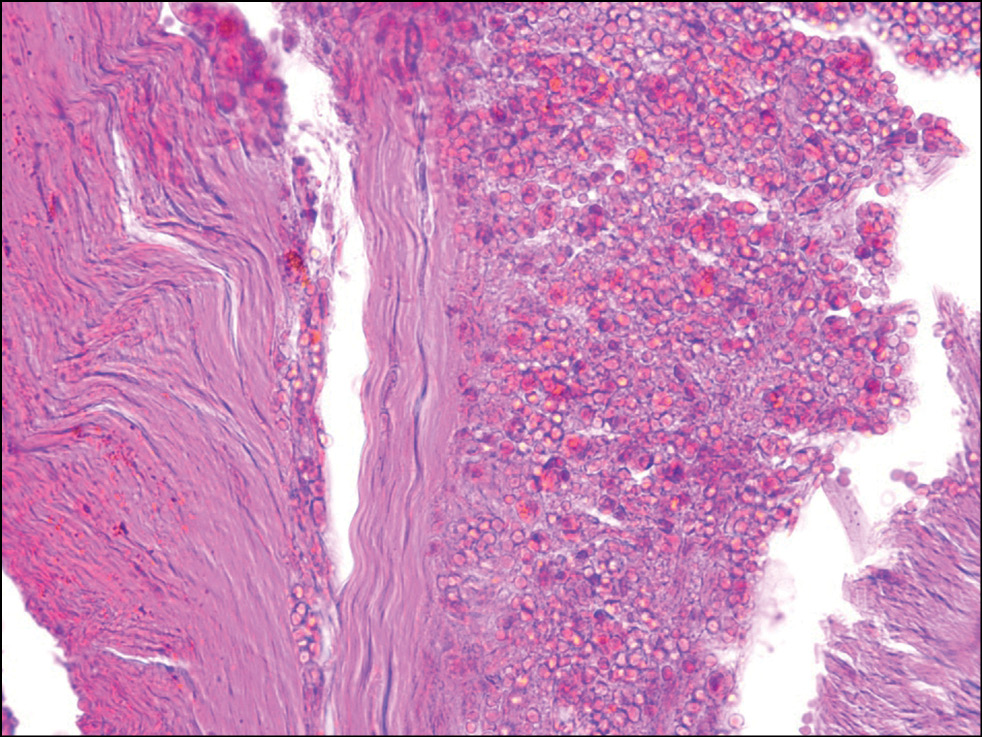

С помощью гистологического исследования установлена давность СДГ у лиц, скончавшихся до оказания медицинской помощи. В 65% случаев видимых реактивных изменений в СДГ не установлено, что могло соответствовать возрасту её образования менее 1 часа. В 20% случаев реактивные изменения соответствовали временному интервалу возраста СДГ от 12 до 24 часов (рис. 1), в 15% случаев ― от 24 до 48 часов (рис. 2).

Рис. 1. Субдуральная гематома с установленной давностью 12–24 часа. Окраска гематоксилином и эозином, ×400.

Fig. 1. Subdural hematoma with an established prescription of 12–24 hours. Coloring: hematoxylin and eosin, ×400.

На сегодняшний день известно, что в первые 12 часов травмы происходит начальное отложение фибрина и полиморфноклеточная миграция в свёрток со стороны его дуральной поверхности. От 12 до 24 часов в гематоме определяются начальная миграция фибробластов и фагоцитоз эритроцитов. Новообразованная мембрана визуализируется ориентировочно через 4 дня, отчётливой она становится к 10-м суткам. Неоваскуляризация отмечается не ранее чем через 5 суток. Определение калибра новообразованных сосудов при этом может вызывать трудности, поскольку этот критерий субъективен и не стандартизирован. Стоит отметить также, что толщина новообразованной мембраны должна анализироваться только относительно объёма гематомы. Если данные о размере и объёме сгустка неизвестны, то толщину неомембраны не следует брать во внимание при установлении давности СДГ [8].